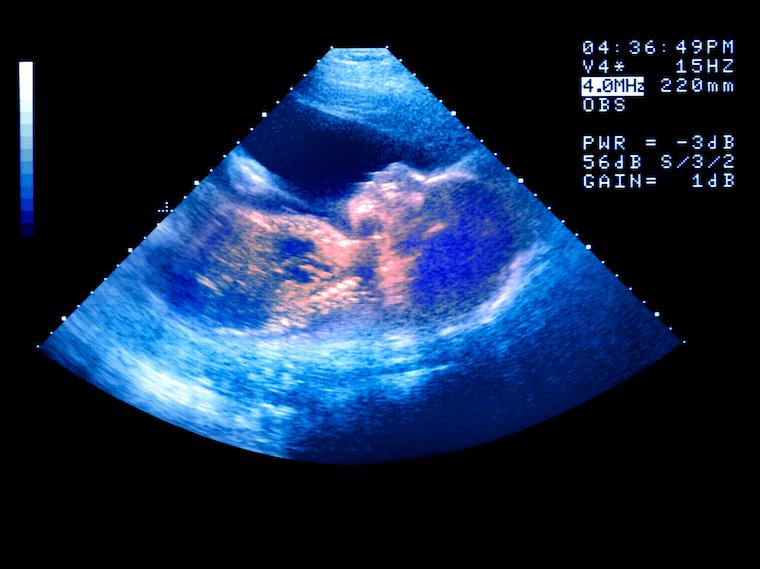

Losing Weight Doesn't Help Pregnancy Odds

A new study questions the conventional wisdom that weight loss benefits fertility odds for women with obesity.